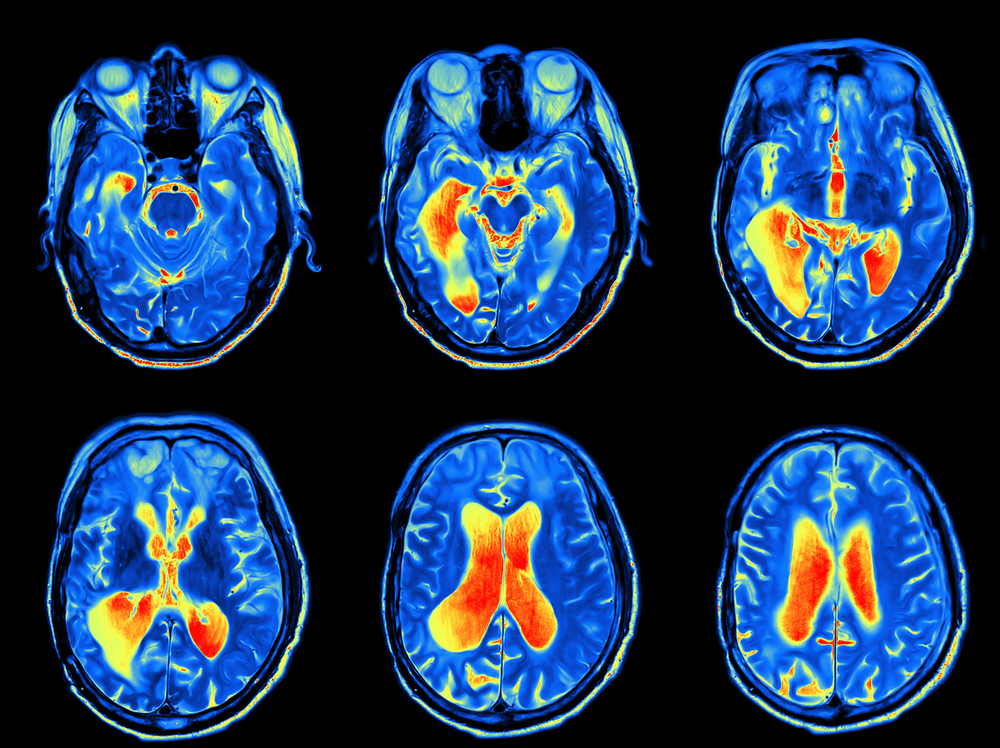

RISONANZA MAGNETICA APERTAUna nuova Risonanza Magnetica Aperta ad alta definizione è attiva in Roma presso Diagnostica Nobiliore (Zona Tuscolano Cinecittà - pochi metri dalla Metro A Giulio Agricola). E' una Risonanza Aperta Total Body in grado di eseguire esami articolari (Mano, Polso, Gomito, Ginocchio, Caviglia, Piede), Spalla, Anca, Colonna Lombare, Dorsale e Cervicale ed Esami della Mandibola e dell'Encefalo. REFERTI IN POCHE ORE

La “Risonanza Magnetica Aperta” è dedicata allo studio delle articolazioni e del rachide: ginocchio, polso, gomito, mano, caviglia, spalla, anca, colonna cervicale-dorsale, lombo-sacrale. Prezzi a partire da 50 Euro. Immagine sul sito. Molto Comoda. L’apparecchiatura consente di produrre immagini ad alta risoluzione con il massimo comfort. L’apparecchiatura consente di produrre immagini ad alta risoluzione, non produce interazioni negative con i tessuti corporei, ed è studiata per migliorare il comfort del paziente. Grazie alla caratteristica di essere “aperta”, facilita l’approccio all’esame per pazienti che soffrono di claustrofobia. Apparato nuovo. Cranio, Colonna Cervicale, Dorsale, Lombare, Anca, Spalla, Ginocchio, Caviglia, Piede, Gomito, Polso, Mano. Permette, nei casi più gravi di claustrofobia, la presenza di un parente o di un conoscente all’interno della sala diagnostica, oltre a quella del personale tecnico, che monitora la situazione. La macchina facilita l’approccio all’ esame per pazienti che soffrono di claustrofobia. Le immagini sono fornite su supporto CD per una approfondita analisi da parte del Radiologo Specialista. I referti sono disponibili entro poche ore. Di seguito l'immagine della macchina:

Diagnostica Nobiliore utilizza una Risonanza Aperta Total Body a basso campo molto silenziosa durante l'esame. L’apparecchiatura, studiata per migliorare il comfort del paziente, consente di produrre immagini ad alta risoluzione e non produce interazioni negative con i tessuti corporei.

Le immagini sono fornite su supporto CD per una approfondita analisi da parte del Radiologo Specialista. Cosa è esattamente la Risonanza Magnetica aperta?Una Risonanza Magnetica Nucleare, o RMN, è una tecnica radiologica basata su di un campo magnetico. Rispetto alle risonanze magnetiche “chiuse”, a tunnel, la Risonanza Magnetica aperta riduce l’ansia nei soggetti claustrofobici. Permette la presenza diretta da parte di un accompagnatore all’interno della sala esami per rassicurare il paziente ansioso. L’esame è molto più accettabile per determinate categorie di pazienti come bambini, anziani e persone in sovrappeso. A cosa serve la Risonanza Magnetica aperta a basso campo?La Risonanza Magnetica è impiegata per lo studio dell’apparato muscolo-scheletrico, piccole articolazioni (mano e piede) e per lo studio di distretti più estesi come Colonna, Anca, Spalla, Ginocchio, Caviglia, Gomito ma anche Mandibola ed Encefalo. Sono previste norme di preparazione?Non è necessario nessun tipo di preparazione. Chi NON può effettuare l’esame?Non possono sottoporsi a questo esame il portatore di pacemaker di vecchia generazione o di dispositivi ad attivazione magnetica come elettrodi e neurostimolatori, e i portatori di protesi ferromagnetiche di non accertabile compatibilità con i campi magnetici. Nel caso esistano dubbi sulla presenza nel corpo di parti metalliche (punti di sutura, clip, protesi) il paziente dovrà informarne il personale medico e paramedico. La risonanza magnetica aperta è dolorosa o pericolosa?L’esame non è né pericoloso né doloroso. Rispetto ad altre metodiche di diagnostica per immagini la risonanza magnetica presenta diversi vantaggi: possibilità di ottenere sezioni multiplanari ad elevata risoluzione con riconoscimento dei diversi tessuti senza impiego di radiazioni ionizzanti. Come funziona?La risonanza magnetica viene effettuata senza impiego di raggi x: vengono utilizzati un campo magnetico e onde di radiofrequenza analoghe a quelle delle trasmissioni radio-televisive. Quanto dura l’esame?L’esame viene eseguito con metodiche accurate ed ha una durata di circa 20 minuti a tratto. E’ possibile eseguire sequenze più brevi ma con limiti all’accuratezza dell’esame. Cosa viene consegnato al paziente?Diagnostica Nobiliore è dotata di strumenti software all’avanguardia che permettono di presentare al paziente un Referto dettagliato con immagini stampate su carta a corredo di quanto rappresentato nel referto. Nel plico consegnato al paziente è incluso un CD che contiene tutte le immagini rilevate ed un software ad apertura automatica per l’esame delle immagini. Il paziente o un suo medico può esaminare le immagini dettagliate semplicemente inserendo il CD in un lettore di un PC.